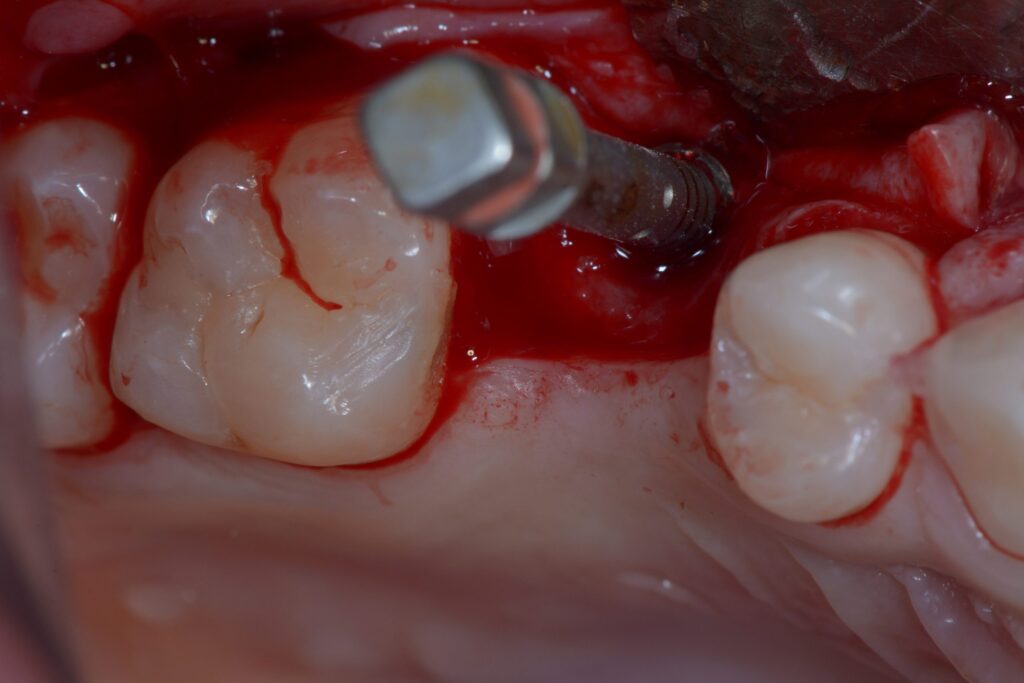

Severe Persistent Pain After Implant Surgery

Pain lasting more than 5 days after dental implant surgery is a major warning sign. While mild to moderate discomfort is normal for the first 3-4 days, intense throbbing pain unrelieved by standard medications may indicate infection, nerve damage, or severe inflammation. This pain often accompanies other symptoms like fever, increasing swelling, or pus discharge, requiring immediate dental evaluation. Importantly, implant-related infection pain typically worsens at night and may radiate to the ear or temple.

If experiencing such pain, see your dentist immediately, as it may indicate potential causes of implant failure, which they’ll diagnose through clinical examination and possibly X-rays. Treatment may involve antibiotics, infection drainage, or, in severe cases of dental implant failure, removal. Sometimes, persistent pain stems from improper implant pressure on bone or nerves, requiring adjustment or replacement. Preventing implant failure includes choosing an experienced surgeon, strict post-op care, and avoiding smoking/alcohol.

Abnormal Swelling After Implant Surgery

In cases of failed implant treatment, while some swelling is normal for the first 2-3 days post-surgery, swelling that intensifies or spreads after day three often indicates infection or severe inflammatory complications requiring immediate professional evaluation. This abnormal swelling typically comes with skin redness, warmth in the area, and throbbing pain. In acute cases, patients might experience mild fever. Swelling that worsens daily, especially when accompanied by difficulty opening the mouth, requires immediate attention.

This progressive swelling often results from bacterial infection, foreign body reaction, or abscess formation. Your dentist may prescribe antibiotics or, if an abscess forms, drain it. While cold compresses help initially (first 48 hours) and warm compresses afterward can reduce swelling, persistent swelling beyond 5 days demands professional evaluation. When left untreated, such swelling could contribute to dental implant failure. Prevention includes maintaining oral hygiene, taking prescribed antibiotics, and avoiding strenuous post-surgery activities.

Prolonged Bleeding After Implant Surgery

Some bleeding is normal for the first 24-48 hours after implant surgery, but bleeding beyond this period raises concerns as potential signs of implant failure that require professional evaluation. This could indicate blood clotting disorders, high blood pressure, surgical blood vessel damage, or developing infection. Continuous bleeding, unstopped by sterile gauze – especially with a metallic taste or large blood clots – requires immediate attention, as it might signal potential dental implant failure.

Loose Implant

When an implant moves during clinical examination, it’s one of the clearest signs of treatment problems. This typically occurs due to failed bone integration (osseointegration failure) or progressive bone loss around the implant. Dentists assess mobility using specialized tools like periodontal probes or controlled pressure tests. A loose implant often accompanies other symptoms like pain, gum inflammation, or visible position changes, which could ultimately lead to dental implant failure if unaddressed.

While implant failure can occur due to infection (peri-implantitis), premature loading, insufficient bone density, or surgical factors, our team at D’Amico Dental Care minimizes risks through precise CBCT-guided placement, customized healing protocols, and thorough patient education. Mild cases may be resolved with antibiotics and bite adjustments, but advanced failures often require implant removal, bone grafting, and delayed re-implantation. The key to long-term success lies in meticulous oral hygiene with implant-specific tools, strict adherence to post-op instructions, and regular professional cleanings at our Watertown or Wayland offices – following these guidelines helps ensure your implant remains healthy and functional for decades.

Peri-implantitis: A Serious Threat to Dental Implants

Peri-implantitis is a progressive inflammatory infection in the tissues surrounding an implant and one of the primary causes of implant failure, characterized by distinct symptoms that typically include gum inflammation, redness, bleeding during probing, and, in advanced cases, pus discharge from the area. A probing depth exceeding 4mm with bleeding, combined with visible bone loss on X-rays, confirms the diagnosis. If left untreated, this condition can lead to severe bone deterioration and ultimately dental implant failure, resulting in implant loss.

Mechanical failure in dental implants typically appears as a fracture in one of the implant system’s components (fixture, abutment, or connecting screw), which can be signs of implant failure, often resulting from excessive forces due to teeth grinding (bruxism), improper prosthesis design, or material fatigue after years of use. The most severe type—fixture fracture—usually requires complete implant removal and bone grafting. Symptoms include sudden pain, a loose crown, and changes in bite alignment, all of which could contribute to dental implant failure if ignored.